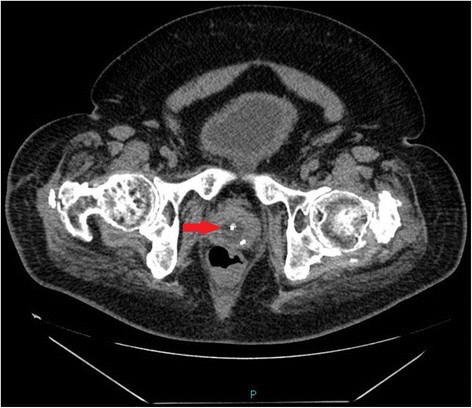

Figure 2From: Missed signs of autonomic dysreflexia in a tetraplegic patient after incorrect placement of urethral Foley catheter: a case reportAxial scan of CT of pelvis performed ten days later: Neither the catheter nor balloon of Foley catheter can be seen inside the urinary bladder. The balloon of Foley catheter (arrow) is located in dilated prostate-membranous urethra.Back to article page